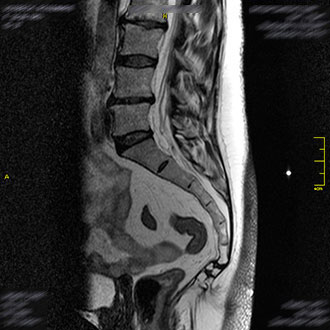

Im Kernspin Zentrum Köln werden alle Abschnitte der Wirbelsäule – Hals-, Brust-, Lenden- sowie Kreuzbeinregion – mit modernster Magnetresonanztomographie untersucht.

Die MRT bietet eine strahlungsfreie und hochauflösende Darstellung von Bandscheiben, Wirbelkörpern, Nerven und dem Rückenmark.

Die MRT des Kreuzbeins und Steißbeins ist besonders hilfreich bei Fehlbildungen, Verletzungen oder Entzündungen im Bereich des Iliosakralgelenks (ISG).

Diese Strukturen sind mit anderen bildgebenden Verfahren oft schwer zugänglich – die MRT ermöglicht hier eine detaillierte, schmerzfreie und strahlungsfreie Darstellung.